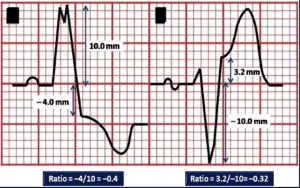

Ein wenig sensitiver ist das modifiziertes Sgarbossakriterium nach Smith (3): Ist die ST- Hebung in einer Ableitung ≥ 25% verglichen mit der S-Welle davor (ausgegangen von der Grundlinie), dann handelt es sich ebenfalls um ein STEMI-Äquivalent . Klingt kompliziert aber einfach Abbildung anschauen:

Abb.: 3: modifizierte Version nach Smith, Berechnung vom ST / S-Verhältnis bei Diskordanz der ST-Strecke. ST-Segment wird am J-Punkt gemessen, aus (2)

(Nicht anwendbar bei extremer Tachykardie, Lungenödem, Hypertonie – diese Patienten haben aber sowieso eine niedrige Schwelle für eine Herzkatheteralarmierung).

Ich glaube hier hat sich eine kleiner Fehler eingeschlichen.

Im Text ist die Rede davon, dass eine ST- Hebung/-Senkung ≥ 25% gegenüber S als postives Kriterium zu werten ist (wie im Beispiel), jedoch ist in dem Algorhithmus von ≤ 0,25 die Rede, was der Angabe im Text widersprechen würde (denn somit wären ja 0,2 oder 20% ST-Veränderung ein positives Kriterium). Es fehlt das Minus (also ≤ -0,25), wie im Orginaltext. Denn eine ST/T Ratio von bsp. -0,4 ist ein positves Kriterium, da es weniger (also <) als -0,25 ist.

(Siehe Figure 3, Cai et al)